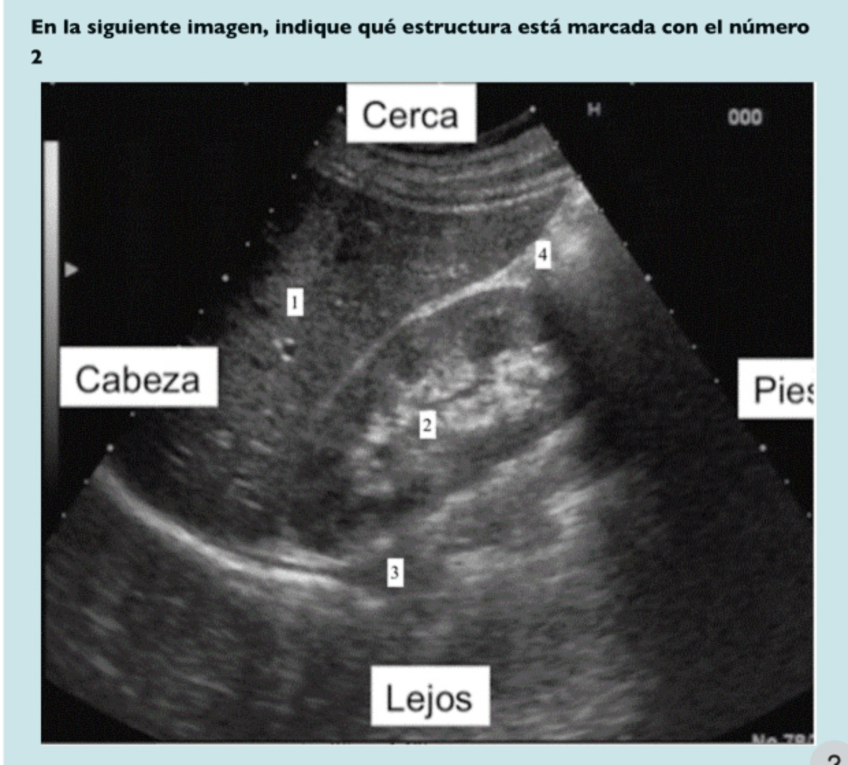

He publicado nuevos practicas de 3º Bases de la Medicina Interna II: evaluacion-ecografia.pdf

PRACTICA-ECOGRAFIA.pdf